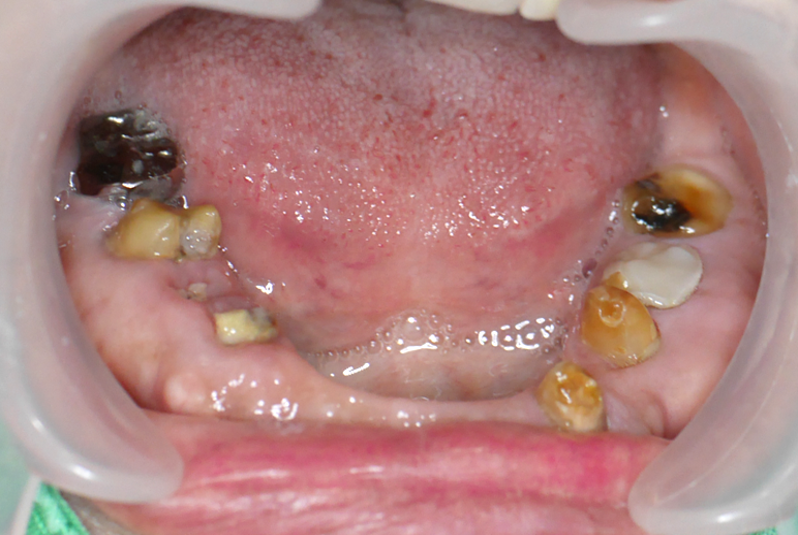

張阿姨的下顎整排假牙已經陪伴她多年。但最近,假牙變得異常鬆動,不僅影響吃飯,更散發出難聞的異味,讓張阿姨非常困擾,甚至不好意思與人交談。最讓她難受的是,幾乎無法好好享用喜歡的食物,生活品質大受影響。

診斷關鍵

經我們詳細檢查發現,問題根源在於支撐假牙的下顎天然牙齒已經嚴重蛀空!這些作為支柱的牙齒結構嚴重損壞,無力再穩固支撐假牙,導致假牙鬆動、藏污納垢產生異味,更無法承受咀嚼力量。